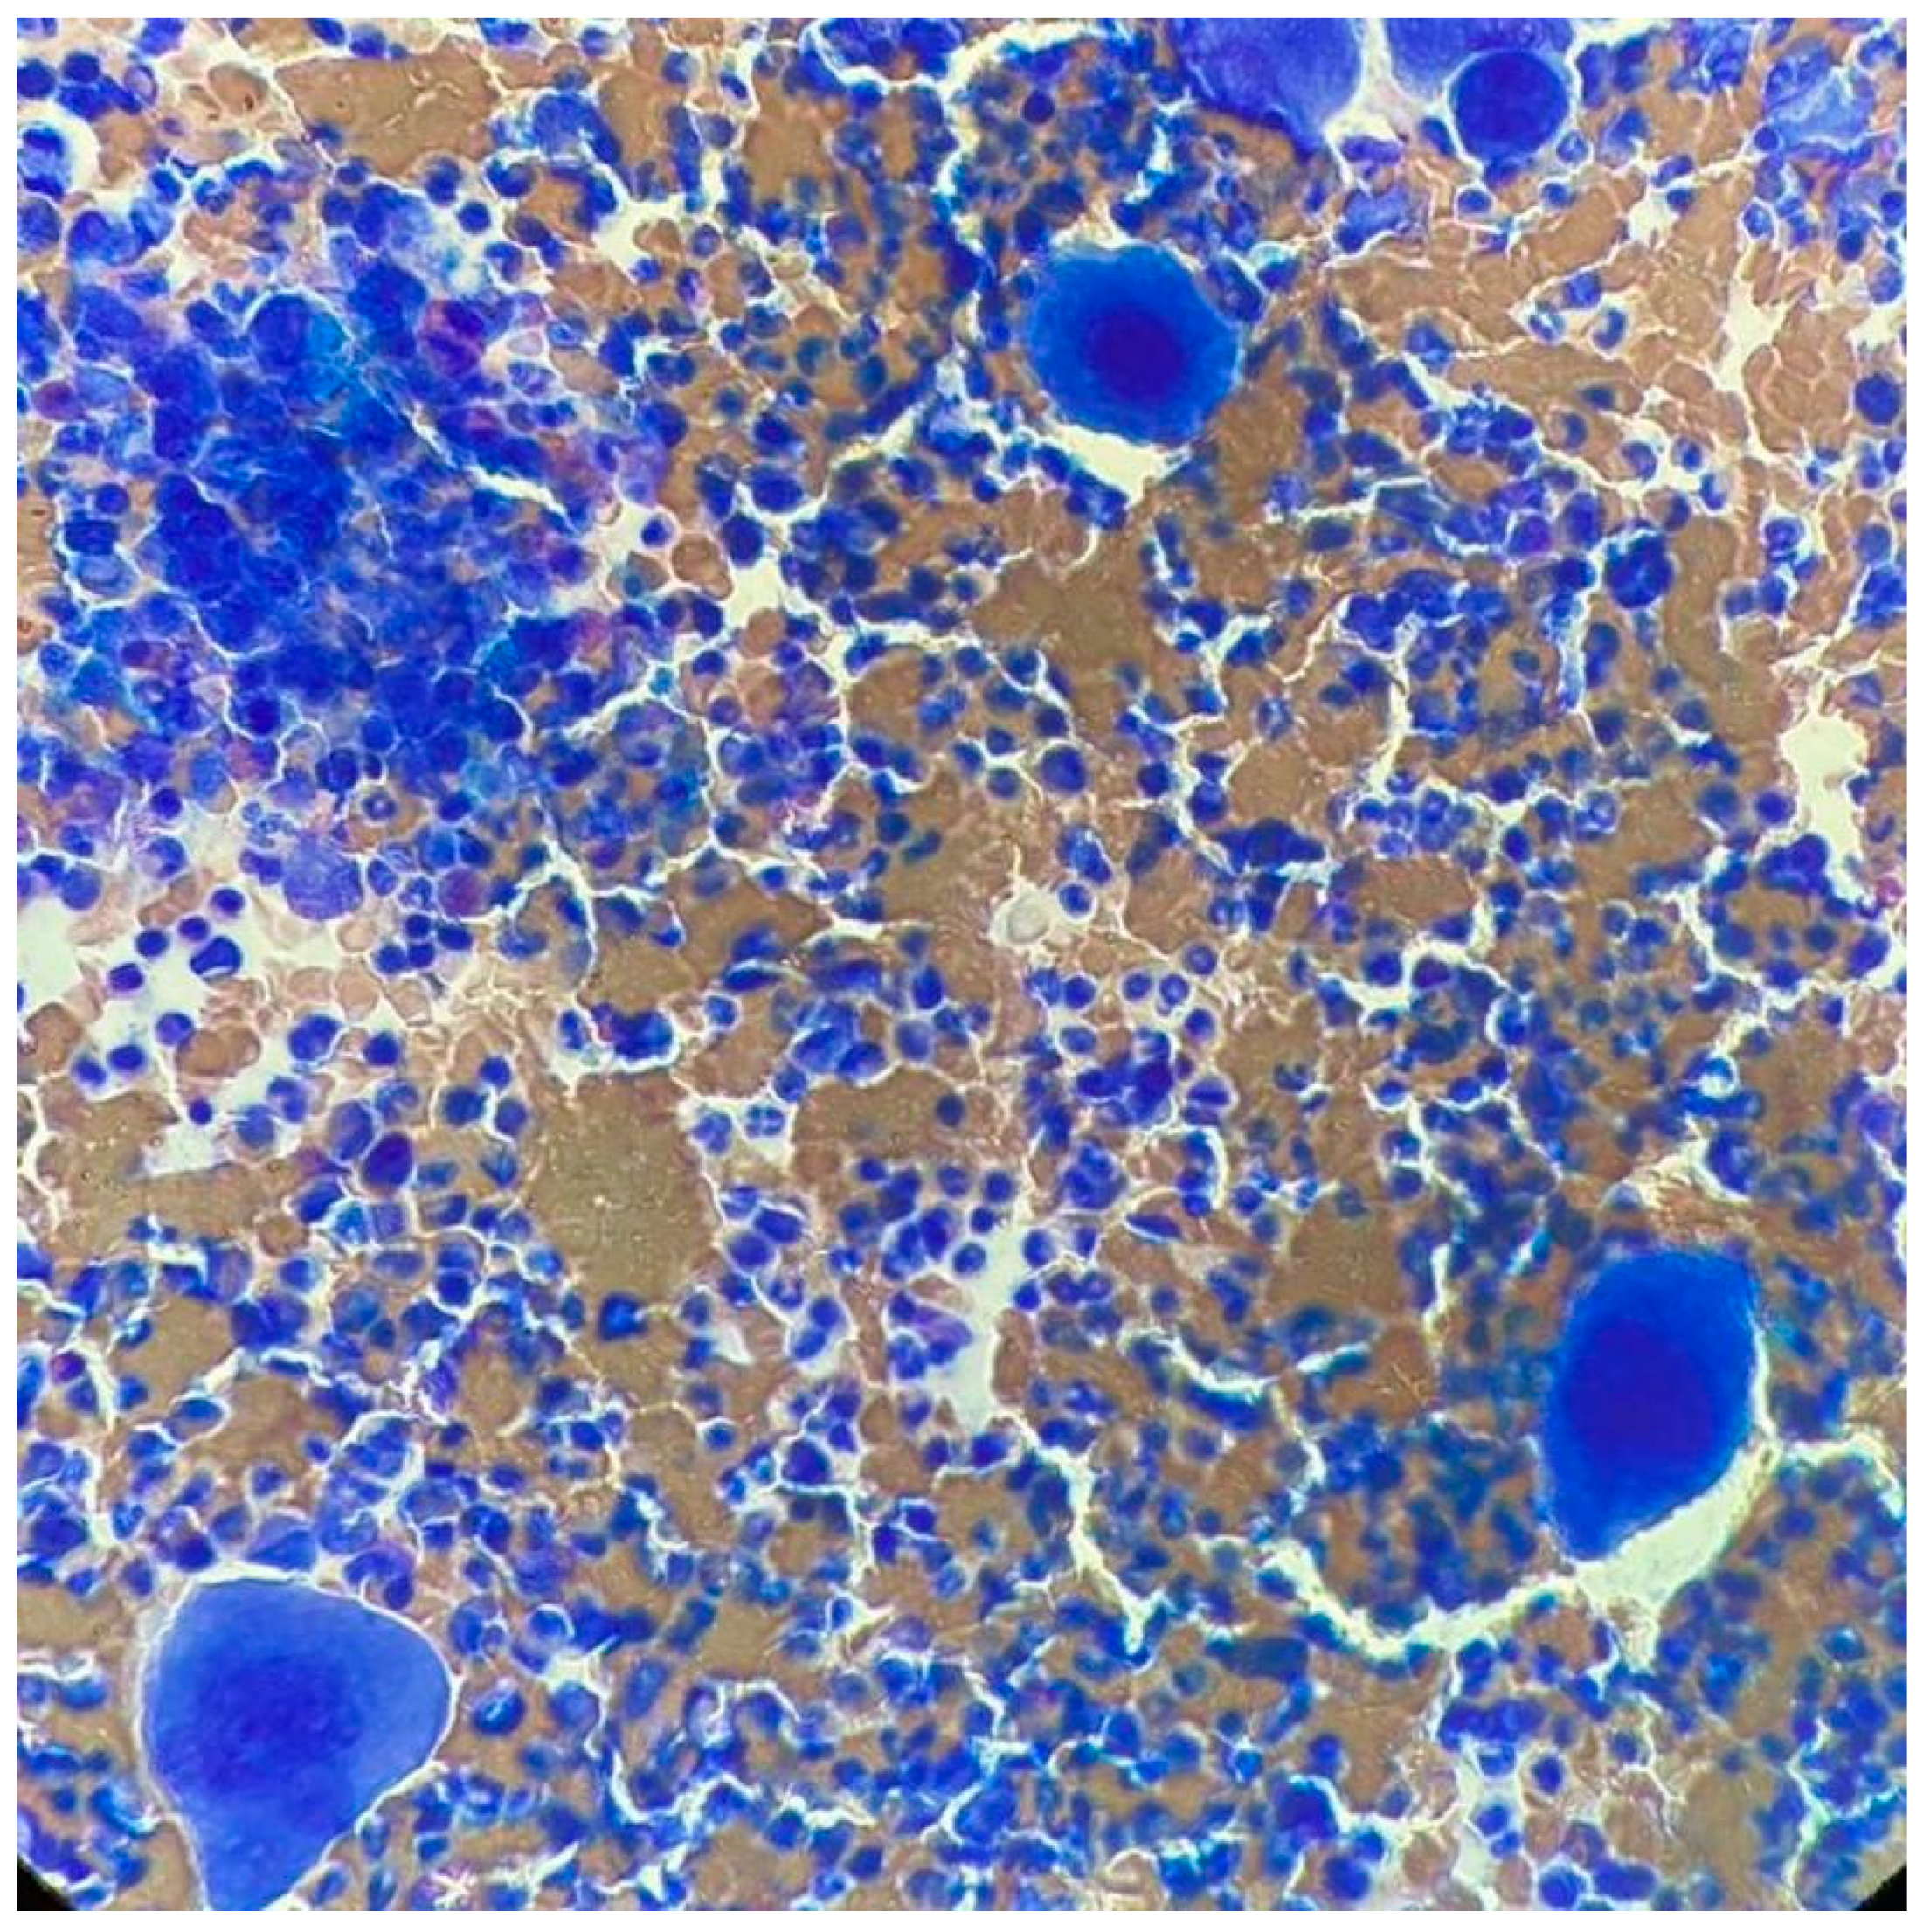

At ITP onset, he showed severe thrombocytopenia; the increase in megakaryocytes in the bone marrow (BM) and the negativity of other tests, including the autoimmunity profile, allowed the diagnosis of ITP. He was treated with steroids, a first line with dexamethasone and a second line with prednisone, enabling only a partial response to be reached. Because of steroid dependency and multiple relapses, he started eltrombopag in September 2011, initially at the dose of 50 mg/day, then reduced to 25 mg/day. In May 2017, he showed hyperleukocytosis; the hemogram profile revealed a white blood cell (WBC) count of 25.9 × 109/L, consisting of 82% neutrophils, 11% lymphocytes, 4% monocytes, 2% basophils, 1% eosinophils, a hemoglobin level of 15.1 g/dL, and platelet count of 800 × 109/L, and the physical examination was negative and no hepatosplenomegaly was observed. After exclusion of infectious origin, he performed second-level exams. The BM smear showed increased cellularity, with a high number of megakaryocytes without blast cells (Figure 1). The BM biopsy revealed a marrow cellularity of 90%, with markedly increased granulocytic series, normal megakaryocytes and reticulin staining. The karyotype was 46, XY, t (9;22) (q34;q11) in all the 10 metaphases analyzed. The real-time quantitative polymerase chain reaction showed the presence of the transcript p210 b3a2. Analysis of JAK2 V617F revealed a positivity of 0.7%, and the screening for CALR and cMPL mutations was negative. Therefore, a diagnosis of chronic-phase CML was made, with low Sokal (0.73), Hasford (695.51) and EUTOS (14) scores, and an intermediate ELTS (2.1065) score. The patient started treatment with imatinib, without cytoreduction and with hydroxyurea.

Figure 1.

Bone marrow smear upon CML diagnosis.